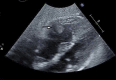

Severe acute respiratory syndrome coronavirus 2 is associated with a prothrombotic state in infected patients. After presenting a case of right ventricular thrombus in a patient with coronavirus disease-2019 (COVID-19), we discuss the unique challenges in the evaluation and treatment of COVID-19 patients, highlighting our COVID-19-modified pulmonary embolism response team algorithm. (Level of Difficulty: Beginner.).